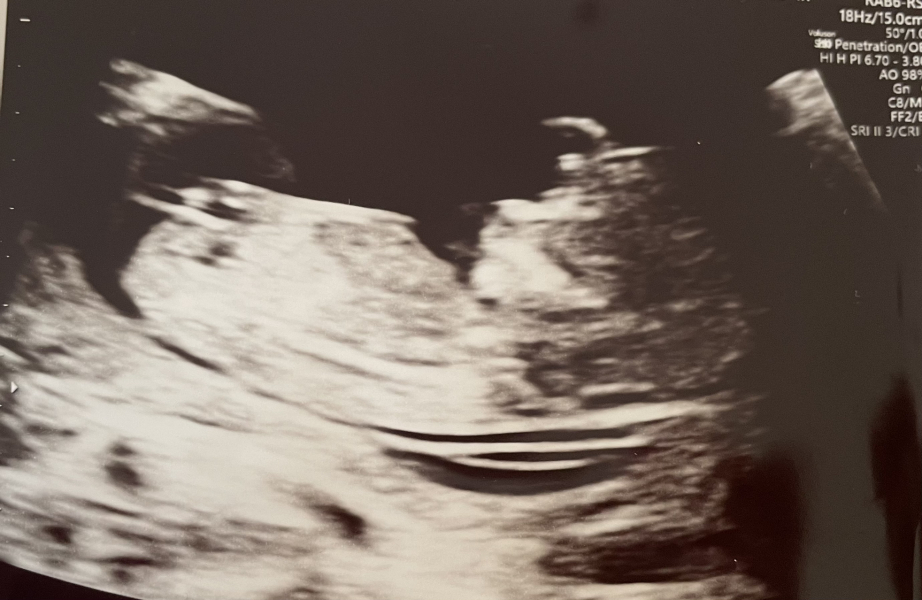

I just wanted to let you know we made it to our dating scan. There were many happy tears. It was so scary after all the sadness we've had and knowing this will be last time we see baby until 20 weeks, but all looked well. Still waiting for the screening results, but they said there were no concerns from the actual ultrasound.

I'm 13+5 today and it still seems surreal. Just wanted to say I think of you all often and hope you're doing well.